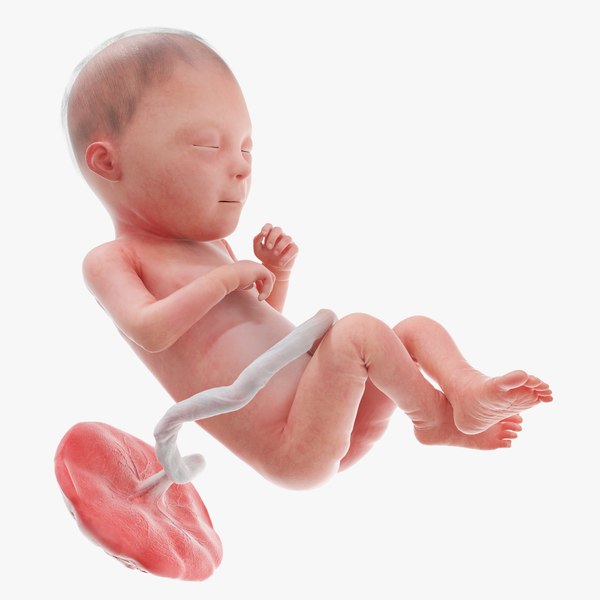

23 недели видео

23 недели видео 113 фотографий